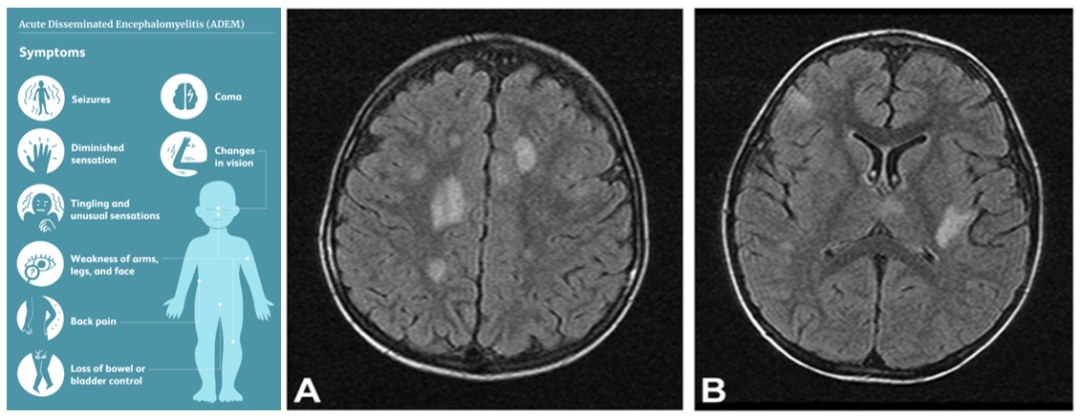

医生又对承承进行了更深入的神经系统查体,除了跟腱反射略亢进外并没有显著异常,然而这时头颅MR显示承承颅内多发片状T2高信号影,真相似乎就在眼前了。

儿童神经内科团队会诊后又给承承进行了脑脊液检查,结果显示MOG(髓鞘少突胶质细胞糖蛋白)抗体滴度升高,至此承承反复发热的病因终于浮出水面:急性播散性脑脊髓炎(ADEM)。